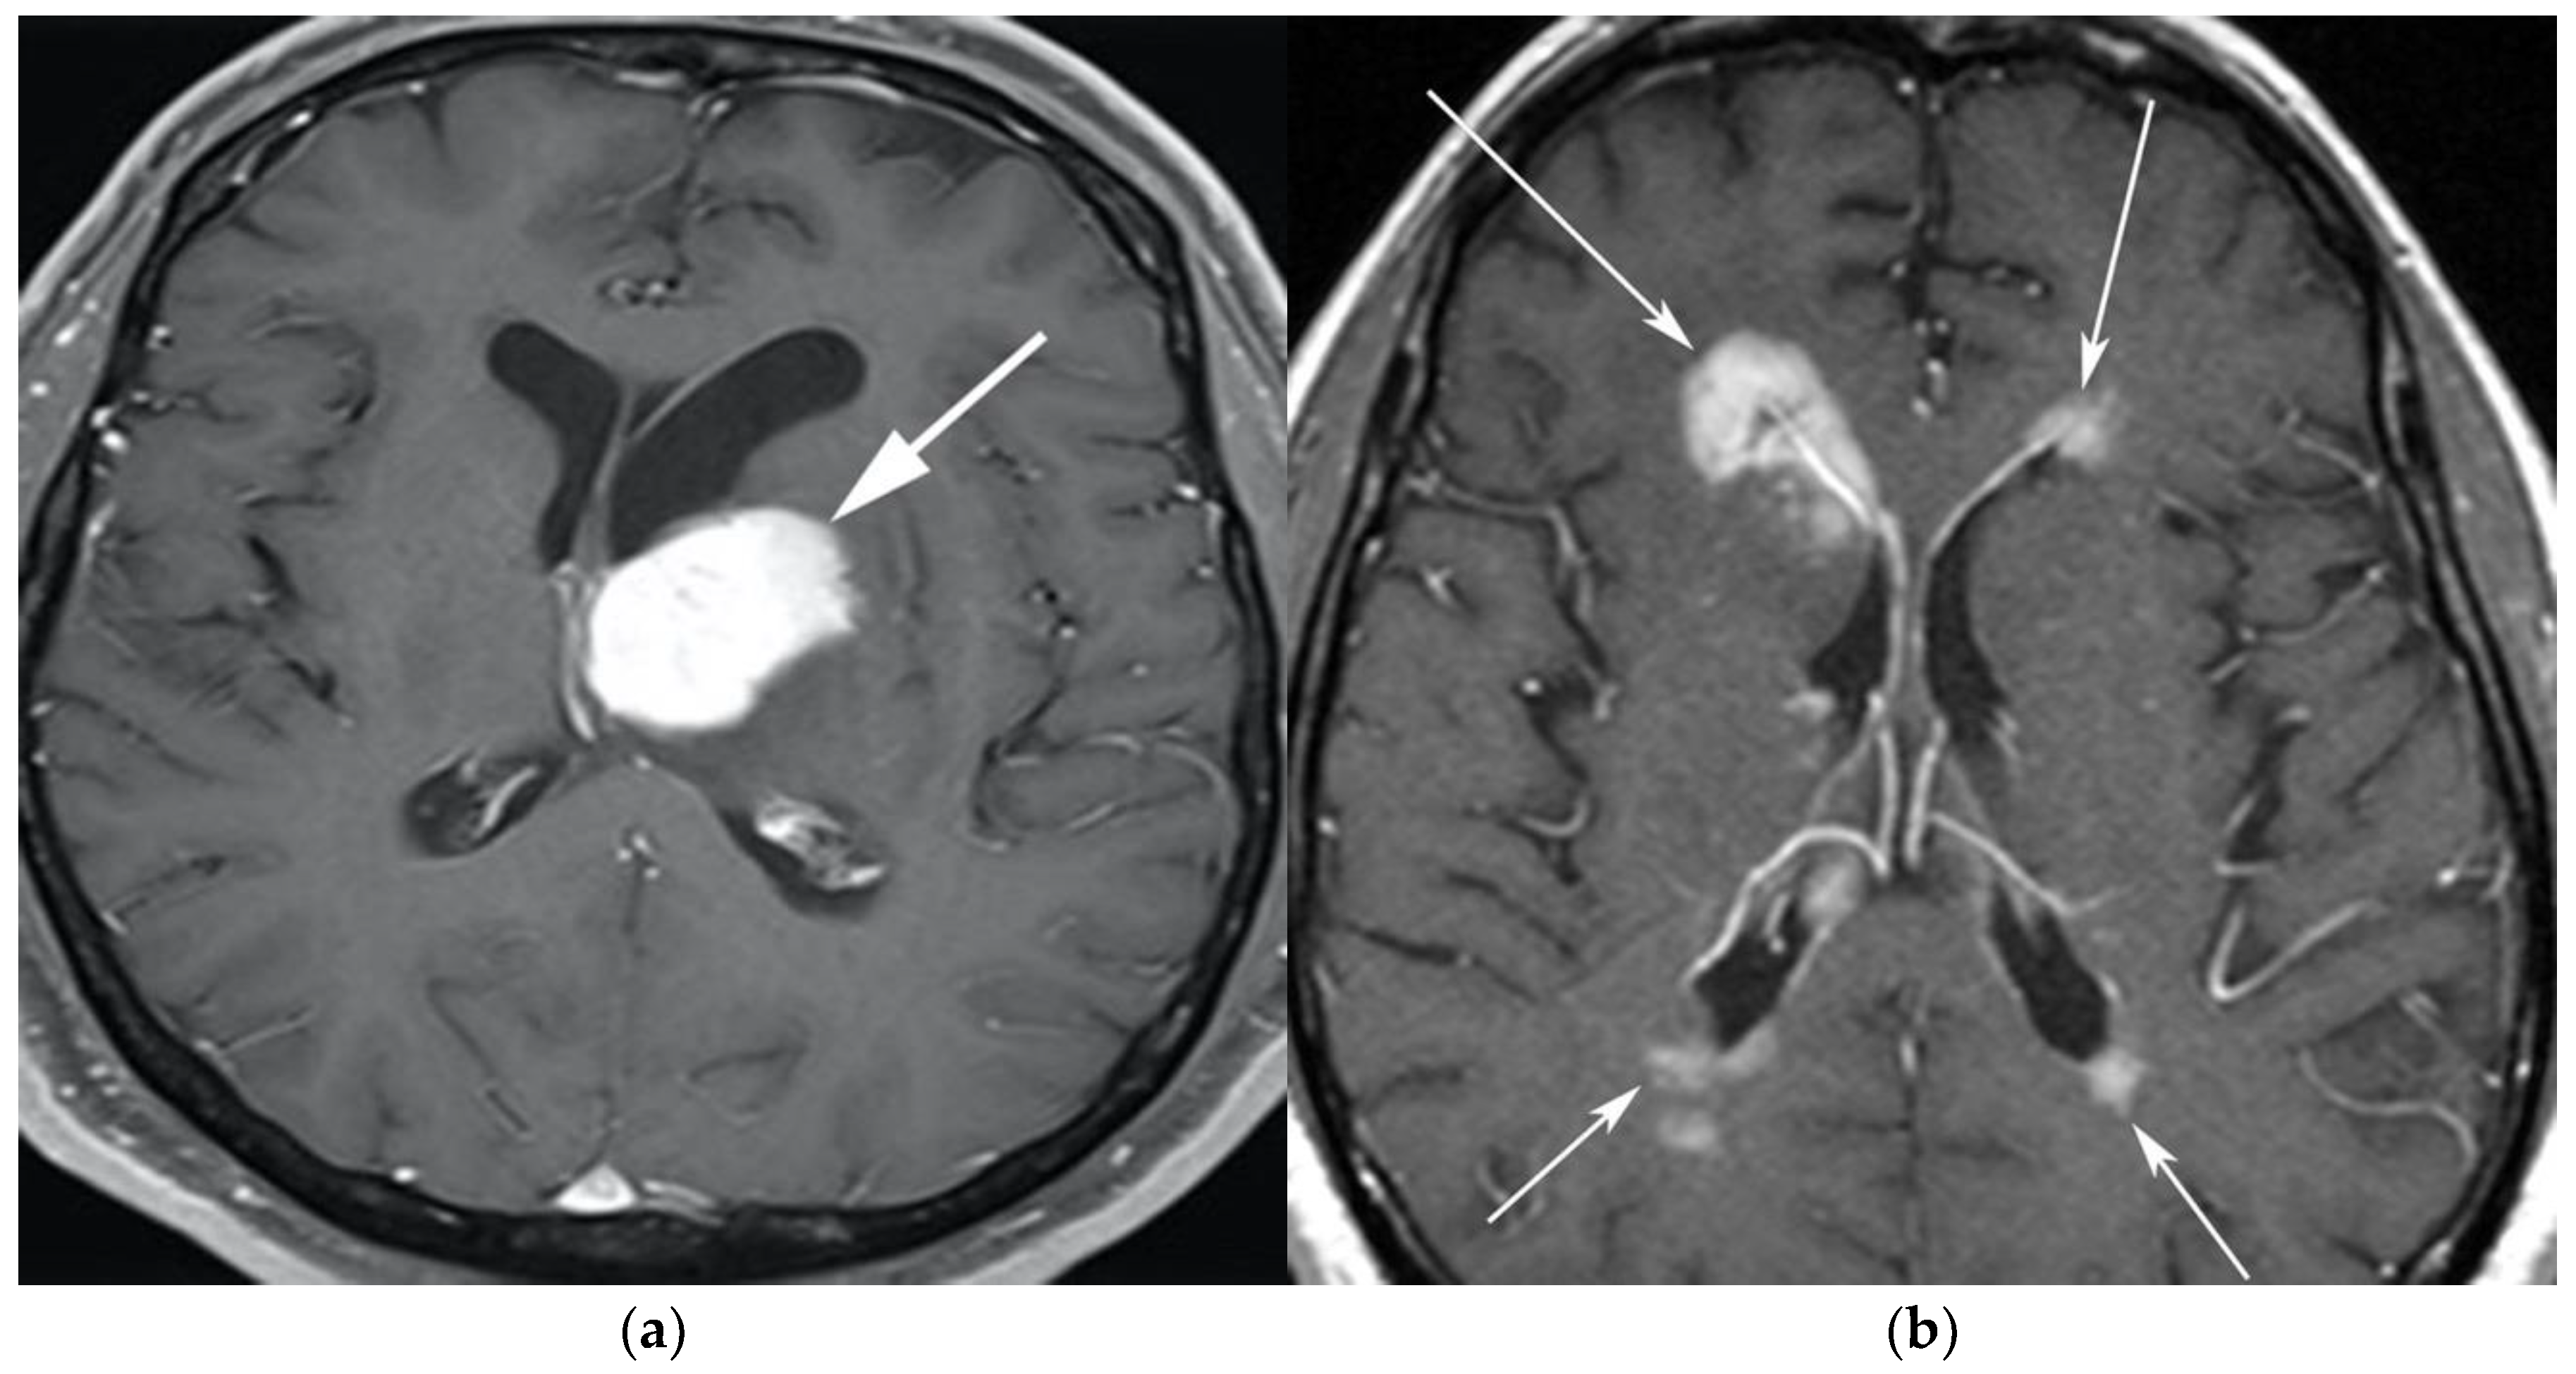

Figure 2.

A 64-year-old-woman presenting with rapid onset of memory deterioration and altered sensorium. (a) Coronal MRI T1 post-contrast images show subtle enhancement along bilateral deep nuclei. At this time, no diagnosis was determined. After 3 weeks, patient presented to emergency department with worsening symptoms. A follow-up MRI was performed. (b) Coronal MRI post-contrast fat-saturated images revealed progressive increase in extent of diffuse infiltrative enhancing masses (white arrows).

Figure 3.

Same MRI series. (a) Axial post-contrast MRI image shows lesions extending caudally to involve the bilateral superior cerebral peduncles and anterior aspect of the mid-brain. (b) Axial MRI T1 post-contrast fat-saturated images show involvement of the posterior limb of the internal capsule and the thalami bilaterally (white arrows). (c) Extension along the lateral aspect of the pons, dentate nucleus, and the middle cerebellar peduncles (white arrows). (d) Axial FDG fused PET/CT image shows increased activity in the aforementioned lesions. Additional hypermetabolic lesions are seen along the course of the corticospinal tract (white arrows). Imaging findings and pattern of involvement are consistent with lymphomatosis cerebri. (e) H&E section shows a tumor composed of large and pleomorphic cells with intermingled small lymphocytes. Primacy CNS lymphoma typically demonstrates an angio-centric predilection. (Original magnification 400×, H&E stain). Other differential diagnoses include a vasculitic process, toxic or metabolic encephalopathy, paraneoplastic syndrome, or acute disseminated encephalomyelitis. Biopsy showed a large non-cohesive B-cell lymphocyte population consistent with LC.